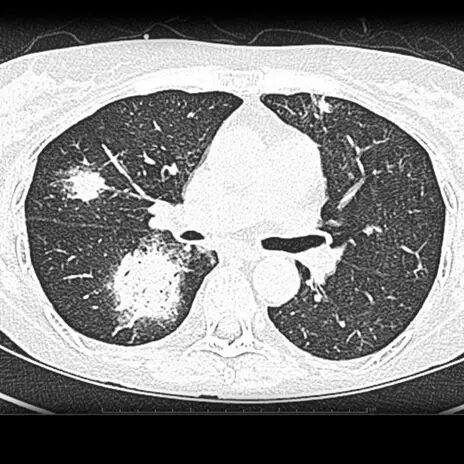

3.1.2 肺曲霉菌感染

高分辩 CT 晕征(Halo sign)指中心结节或肿块周围环形毛玻璃样变或密度略低(与中心比)的区域。. 提示免疫功能低下者曲霉菌感染,常见于非血缘干细胞移植后。